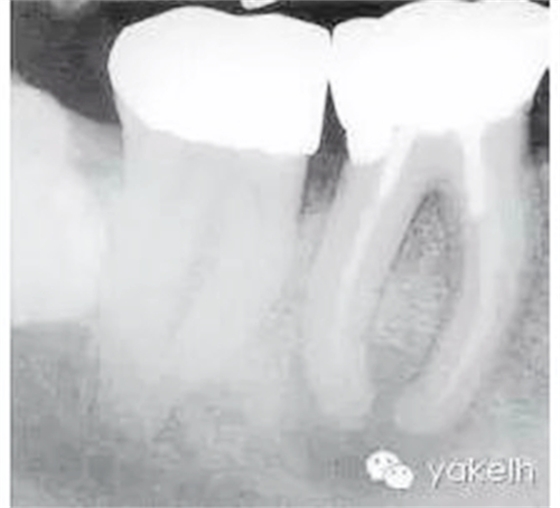

根尖X線片顯示什么(圖5.1.1)?

圖5.1.146術(shù)前X線片,顯示金屬冠修復(fù),每個牙根內(nèi)均有金屬樁,根管充填物均短于放射學根尖且有根尖周透射影。

金屬冠修復(fù)。

近遠中牙根內(nèi)均有金屬樁。

在近中根內(nèi),樁的尖端向根管側(cè)壁偏移。

近遠中牙根均有中度彎曲。

近遠中根管充填物均短于放射學根尖。

近遠中根尖周均有明顯的透射影。

右下頜第三磨牙(48)緊靠右下頜第二磨牙(47)遠中。